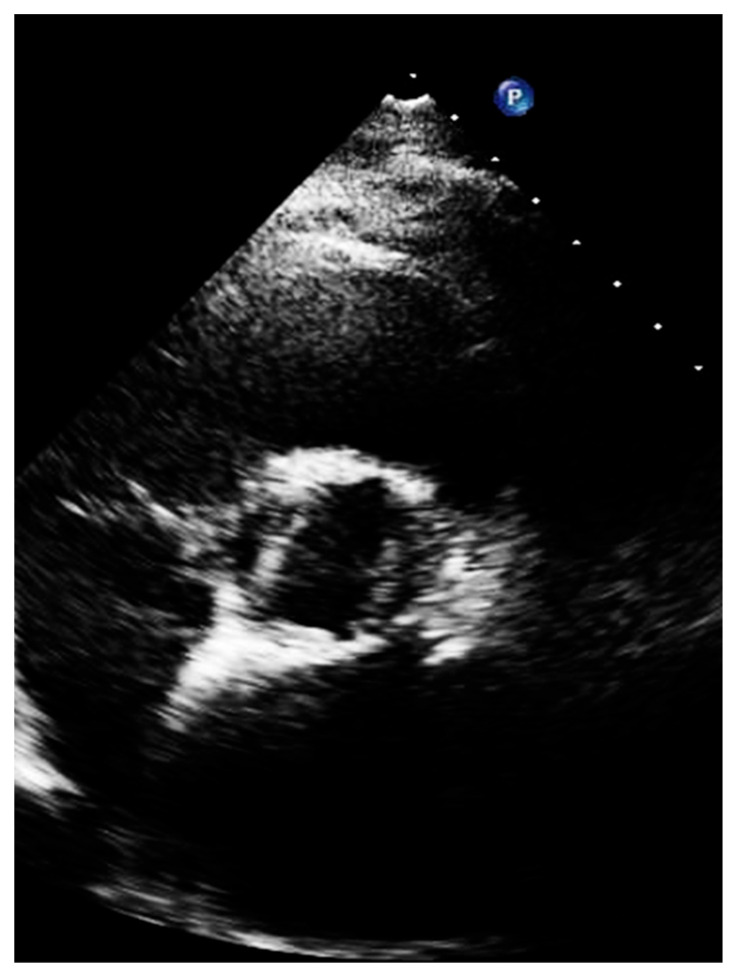

Short axis view. The short axis view visualizes the three aortic leaflets. However, planimetry of the valve may be misleading because the aortic orifice is not planar. From this view, the bicuspid, sclerotic, and calcified aortic valve is diagnosed. In addition, imaging setting optimization, reported for the long-axis view, must also be performed in this view (Figure 6).

Figure 6.

Low gain (left panel), over gain (middle panel), and right gain (right panel) in the short-axis view along the same patient.

A bicuspid valve most often results from fusion of the right and left coronary cusps, so a larger anterior and smaller posterior cusp with both coronary arteries arising from the anterior Valsava sinus is diagnosed in 80% of cases, whereas fusion of the right and non-coronary cusps resulting in larger right than left cusp, with one coronary artery arising from each Valsava sinus, is less common (20% of cases) [24,25,26,27] (Figure 7).

Figure 7.

Short axis of a patient with bicuspid aortic valve, with large left and right cusp.

The short-axis views of the valve in systole should image a typical ‘‘fish-mouth’’ appearance of valve opening and absence of opening at the raphe.